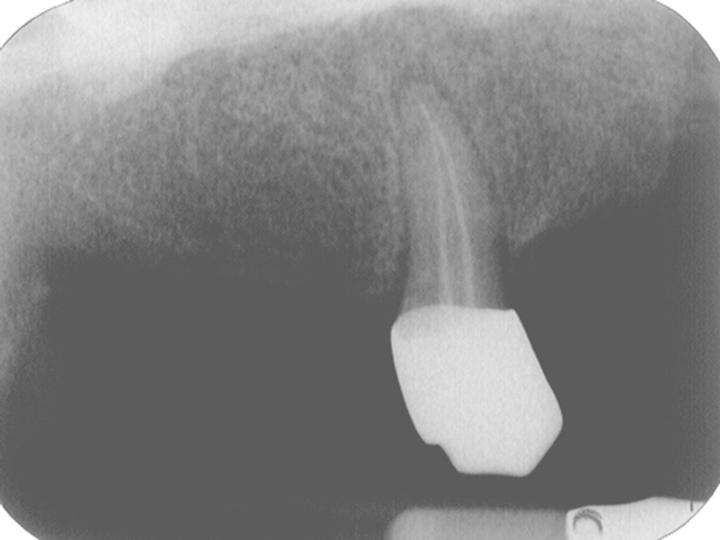

臨床照片 http://oralpathol.dlearn.kmu.edu.tw/dd/2006-D5-CPC-1-data/D5-cpc-1-XRay.JPG

x-ray taking http://oralpathol.dlearn.kmu.edu.tw/dd/2006-D5-CPC-1-data/D5-cpc-1-chart-2.JPG